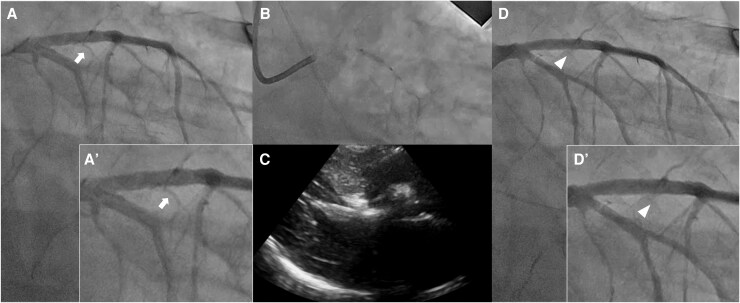

Case summary: A 51-year-old woman was admitted with cerebral haemorrhage and underwent emergency craniotomy. The patient experienced repeated episodes of acute heart failure, leading to several resuscitation attempts and requiring extended MV. Echocardiography revealed severe LVOT obstruction (peak LVOT pressure gradient, 119.7 mmHg). Attempts at volume optimization and pharmacological therapy failed to wean from MV or achieve haemodynamic stability. Given the patient's critical condition, rescue PTSMA was performed, which significantly reduced the LVOT gradient, thereby allowing aggressive volume reduction with haemodialysis and successful extubation within a week.